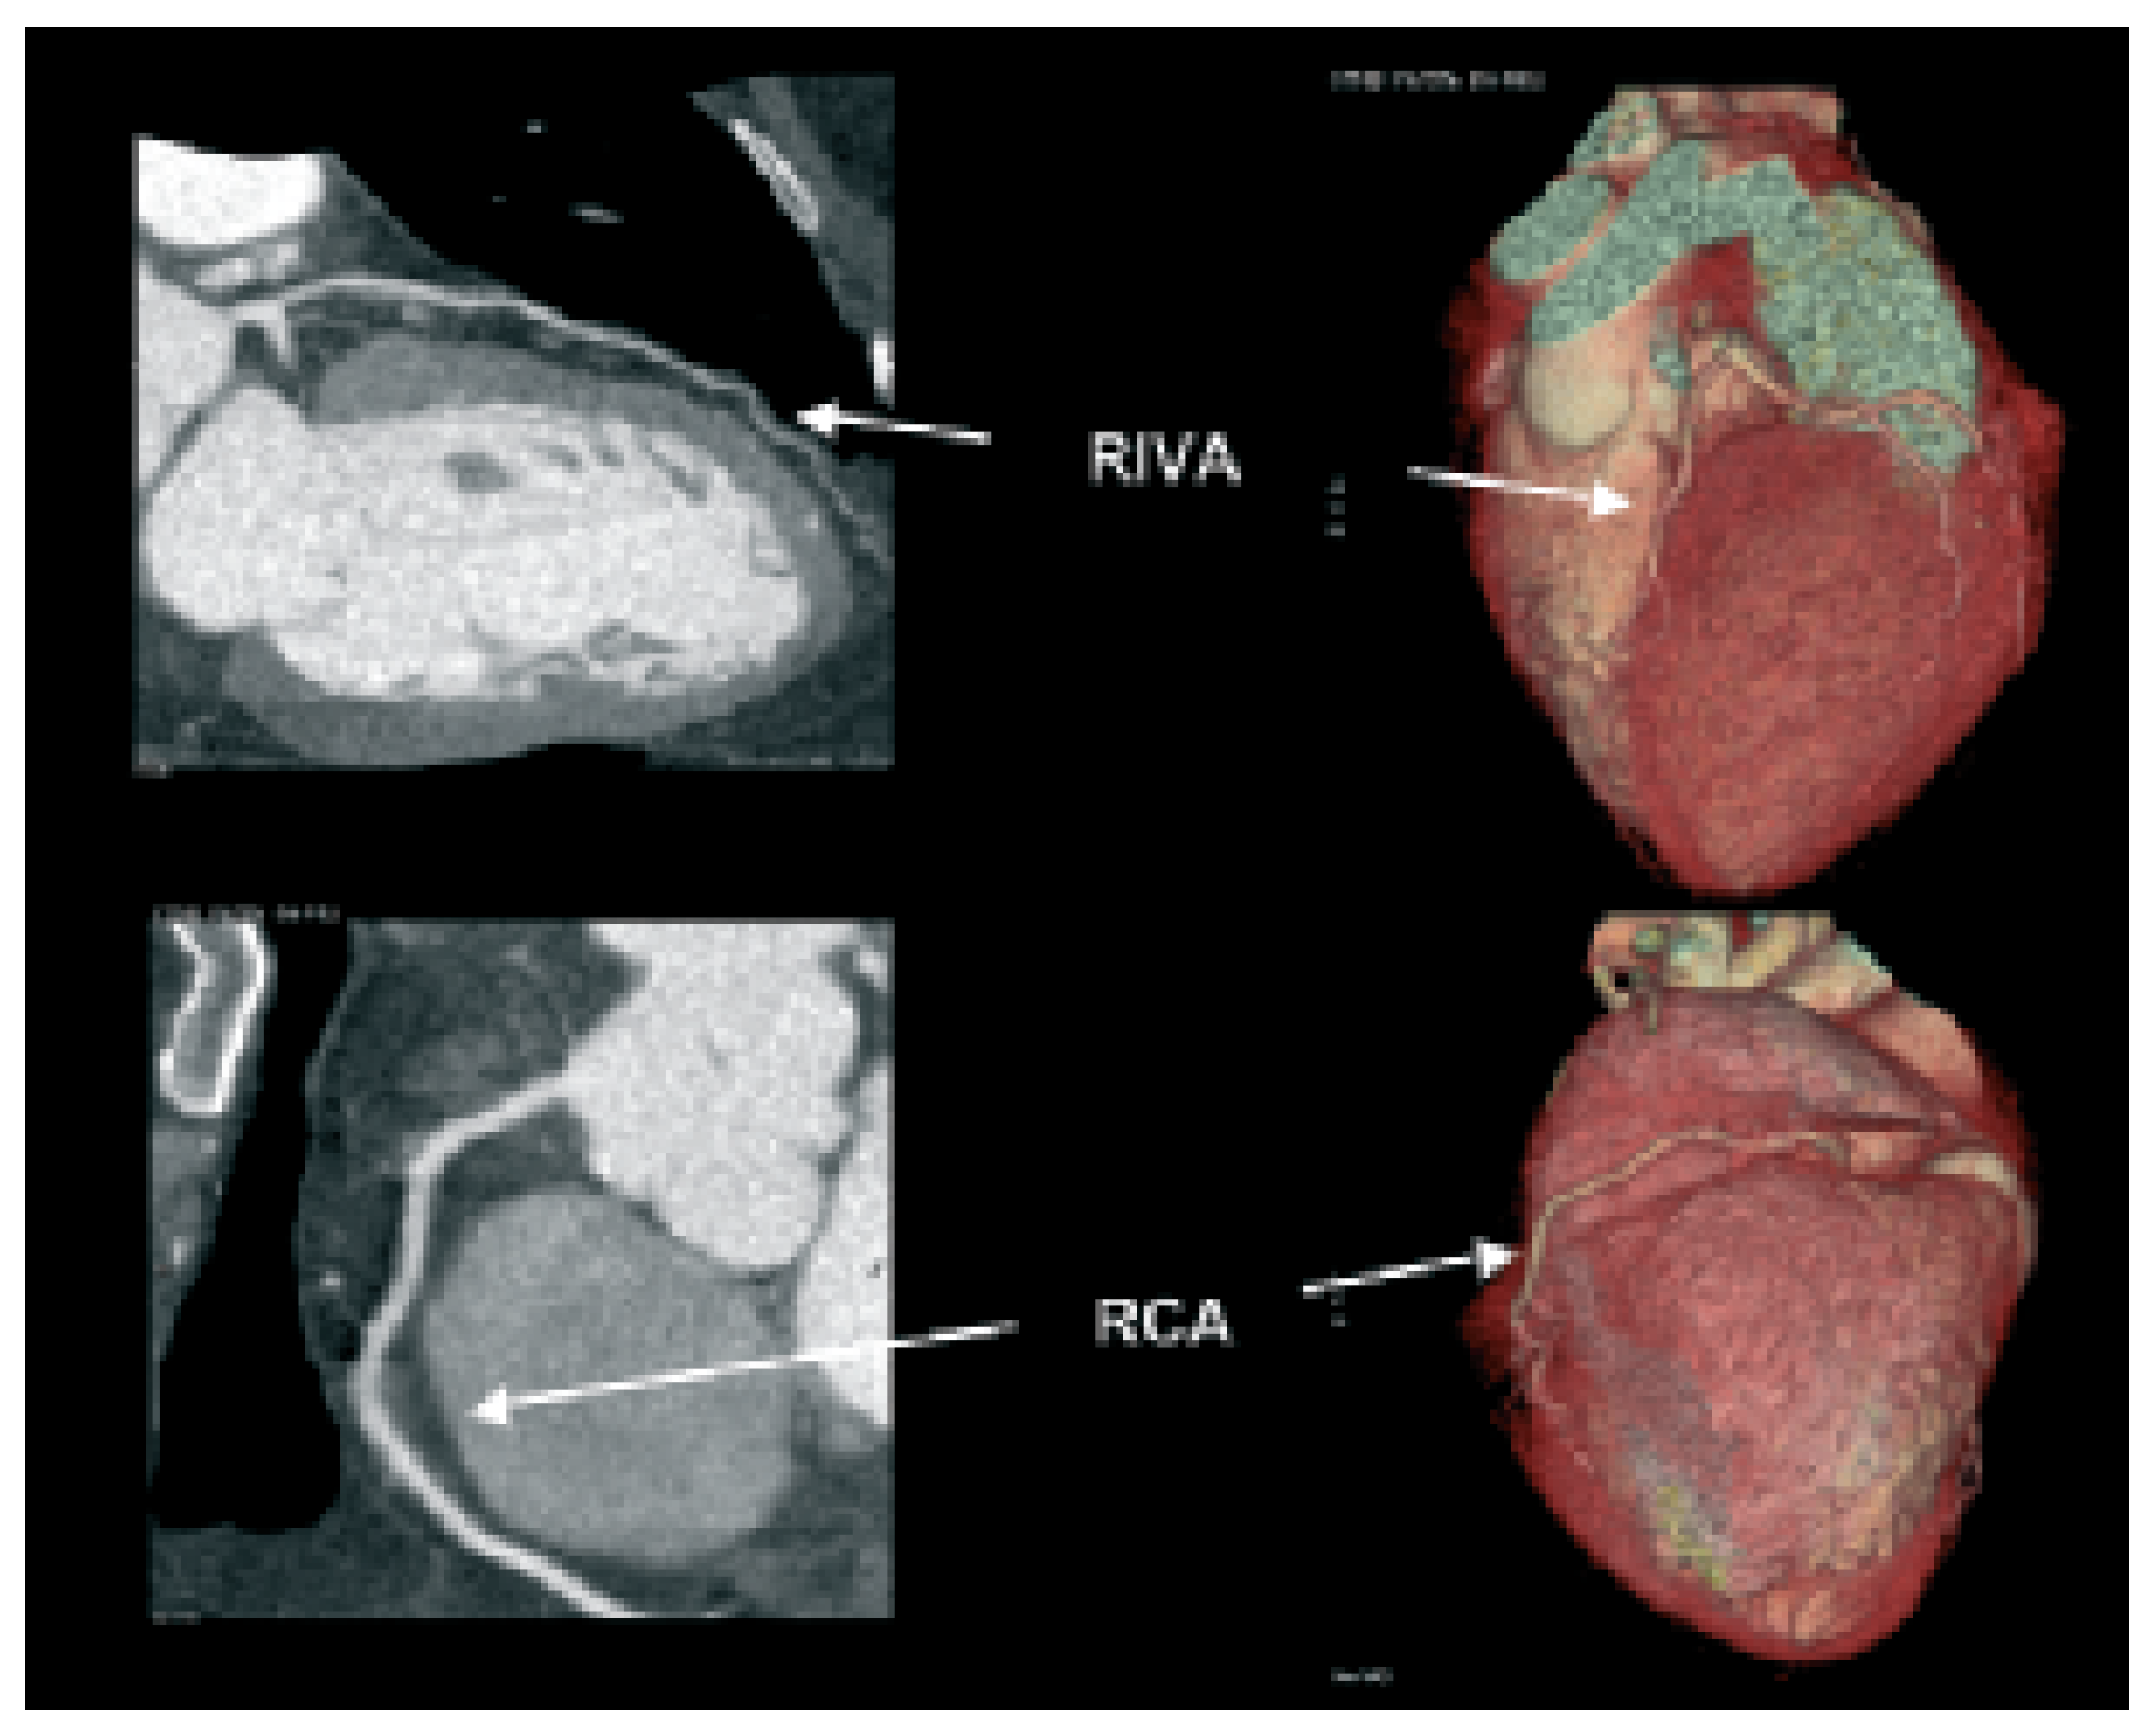

Abbildung 2. Darstellung einer schweren Verkalkung im Ramus circumflexus. Die ausgeprägte Verkalkung verunmöglicht eine korrekte Beurteilung bezüglich Lumeneinengung (links). Mit geeigneten Massnahmen bei der Bildverarbeitung kann dieses Problem teilweise etwas kompensiert werden.

Verkalkungen der Herzkranzgefässe beeinträchtigen allerdings auch erheblich die Darstellung des Lumens in der computertomographischen Angiographie (Abb. 2). Somit lässt sich in stark verkalkten Gefässen meist nicht sagen, ob es sich nur um ein krankes, d.h. arteriosklerotisch verändertes Koronarsegment handelt, oder ob es auch hämodynamisch relevant eingeengt ist. Vor allem bei älteren PatientInnen und solchen mit Diabetes und/oder Niereninsuffizienz, welche ausgeprägte Verkalkungen aufweisen, ist daher keine schlüssige Beurteilung des Lumens möglich. Zudem kann die EKG-getriggerte Untersuchung bei hoher Herzfrequenz, bei Vorhofflimmern und anderen Rhythmusstörungen, die bei etwa 5% der Patienten zu finden sind, nicht durchgeführt werden. Schliesslich sollte bei Patienten mit schwerer Herzinsuffizienz die Volumenbelastung durch das Kontrastmittel in Betracht gezogen werden. Auch durch Stents verursachte Artefakte stellen ein diagnostisches Problem dar (Abb. 3). Obschon die neuesten CT-Geräte sehr genau die Stent-Länge und den Durchmesser erfassen können, ist eine sichere Beurteilung des Lumens in vielen Fällen noch nicht möglich. Da bei der koronaren Herzkrankheit die Frage nach einer Intervention im Vordergrund steht, sei es eine kathetertechnische Stent-Implantation oder eine Bypass-Operation, ist die Erfassung von Koronarstenosen das Hauptziel dieser Untersuchungen. Entsprechend ist diese Einschränkung der Aussagekraft der computertomograpischen Koronarangiographie durch Gefässwandverkalkungen ein grosser Nachteil dieser Methode. Zusammenfassend ist daher der negativ prädiktive Wert der computertomographischen Koronarangiographie sehr hoch, d.h. bei fehlendem Nachweis von Kalzium und Einengungen lässt sich mit an Sicherheit grenzender Wahrscheinlichkeit eine koronare Herzkrankheit ausschliessen. Der positive prädiktive Wert behandlungsbedürftiger Koronarstenosen ist aber vor allem in der älteren Population, in welcher die koronare Herzkrankheit besonders häufig ist, immer noch stark eingeschränkt (Abb. 4). Unseres Erachtens können momentan wichtige klinische Entscheidungen (wie z.B., ob ein Patient aufgrund des Koronarbefundes mittels ACBPOperation oder PCI behandeln werden muss) nicht ausschliesslich anhand des CT-Befundes gefällt werden. Das Vorhandensein von Gefässverkalkungen hat den Einsatz dieser vielversprechenden Technik auch in anderen Gefässabschnitten (wie in den Karotiden [8,9]) beschränkt.